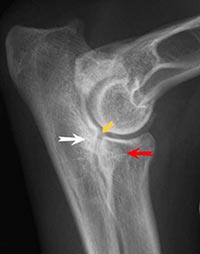

Fragmentierung des Processus coronoideus medialis (FCP, Ablösung des innen liegenden Kronfortsatzes der Elle) Osteochondrosis dissecans am Condylus medialis humeri (OCD, Knorpelablösung am innen liegenden Rollhöcker des Oberarmknochens) Isolierung des Processus anconaeus (IPA, Ablösung des Ellenbogenfortsatzes der Elle)

Ellenbogendysplasie HundEin gleichzeitiges Auftreten mehrerer dieser Komplikationen ist häufig.